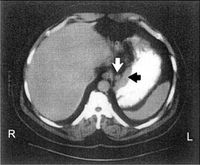

يستخدم التصوير الطبقي المحوري CT-SCAN (الصورة ـ1) والتصوير بالأمواج فوق الصوتية ultrasound و الرنين المغنطيسي MRI scan لتشخيص النقائل وتحديد مرحلة الورم.